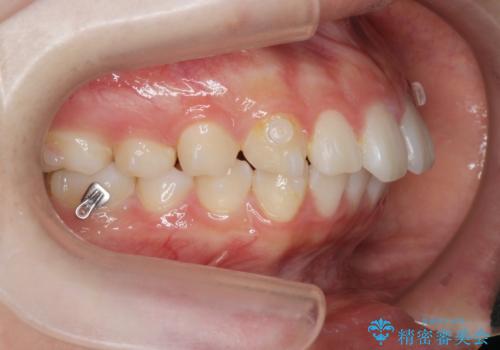

矯正治療を途中でやめてしまった、途中からの治療希望

- 他院での矯正治療中に行かなくなってしまい、装置をつけたまま矯正治療の続きを希望され来院されました。

マウスピースでは並べることが難しい左下の奥歯を部分ワイヤー矯正で並べたのち、マウスピース矯正装置インビザラインで歯並びを整えていきます。